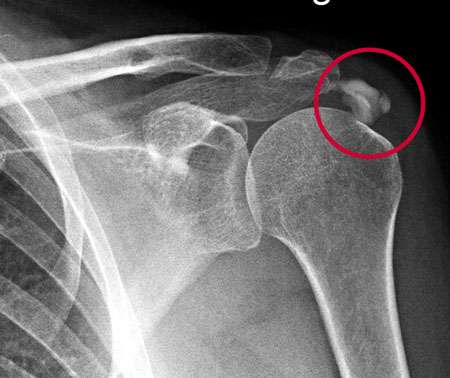

Sobald die Verkalkung eingetreten ist, kann ein Ultraschall oder eine Röntgenuntersuchung die Kalkschulter nachweisen. Eine Kernspinuntersuchung (MRT) ist für die unmittelbare Diagnostik nicht hilfreich, da sich das Kalkdepot hierbei schlecht darstellt. Für die Differentialdiagnose oder Diagnose von Begleiterkrankungen kann ein MRT dennoch sinnvoll sein.

Röntgenbild einer Kalkschulter. Deutlich sichtbar ist die Sehnenverkalkung über dem Schultergelenk (Kreis). © Gelenk-Klinik